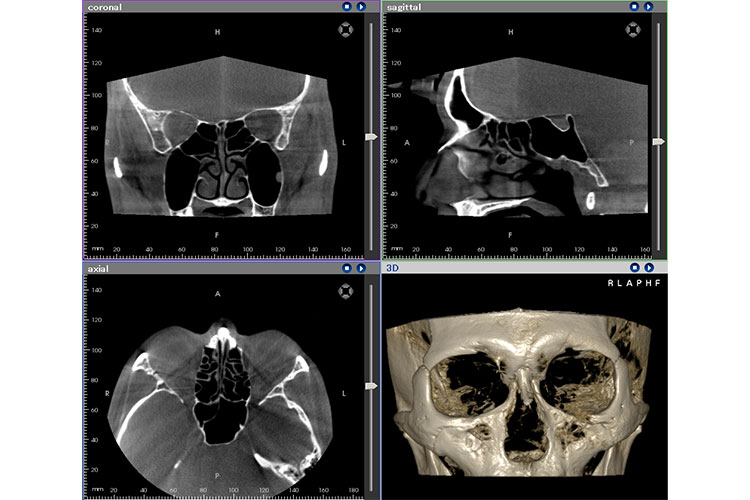

コーンビームCTを用いた耳疾患、鼻疾患の早期発見、早期治療のススメ

副鼻腔炎などの鼻疾患や、滲出性中耳炎などの中耳疾患が疑われる患者さまの確定診断を行うため、画像検査を目的にCT検査を導入しました。当院で導入している「コーンビームCT」とは耳、鼻のみをターゲットとしており、低被曝量、低コストが利点です。撮影後にすぐ診断し治療が可能となります。

CT画像 コーンビームCT機器画像